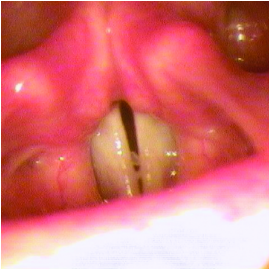

Oral involvement is a common manifestation of PLGD-1 with 32% of patients impacted by these thick, nodular masses on the gums with a distinctly hard, "woody" texture. This condition is known as periodontal disease, ligneous periodontitis, or ligneous gingivitis.1,9,10

With ligneous gingivitis, the gingiva often looks swollen, thickened, firm, and pale, with a characteristic yellowish-white color. Chronic irritation from fibrin deposits and ongoing inflammation can make the gums bleed easily. Over time, persistent fibrin accumulation and inflammation may destroy periodontal tissues, resulting in tooth loss and resorption of the surrounding bone.9,10

Review the lesion image gallery for more examples of ligneous gingivitis.

Ligneous gingivitis caused by congenital plasminogen deficiency type 1, manifesting as gum lesions